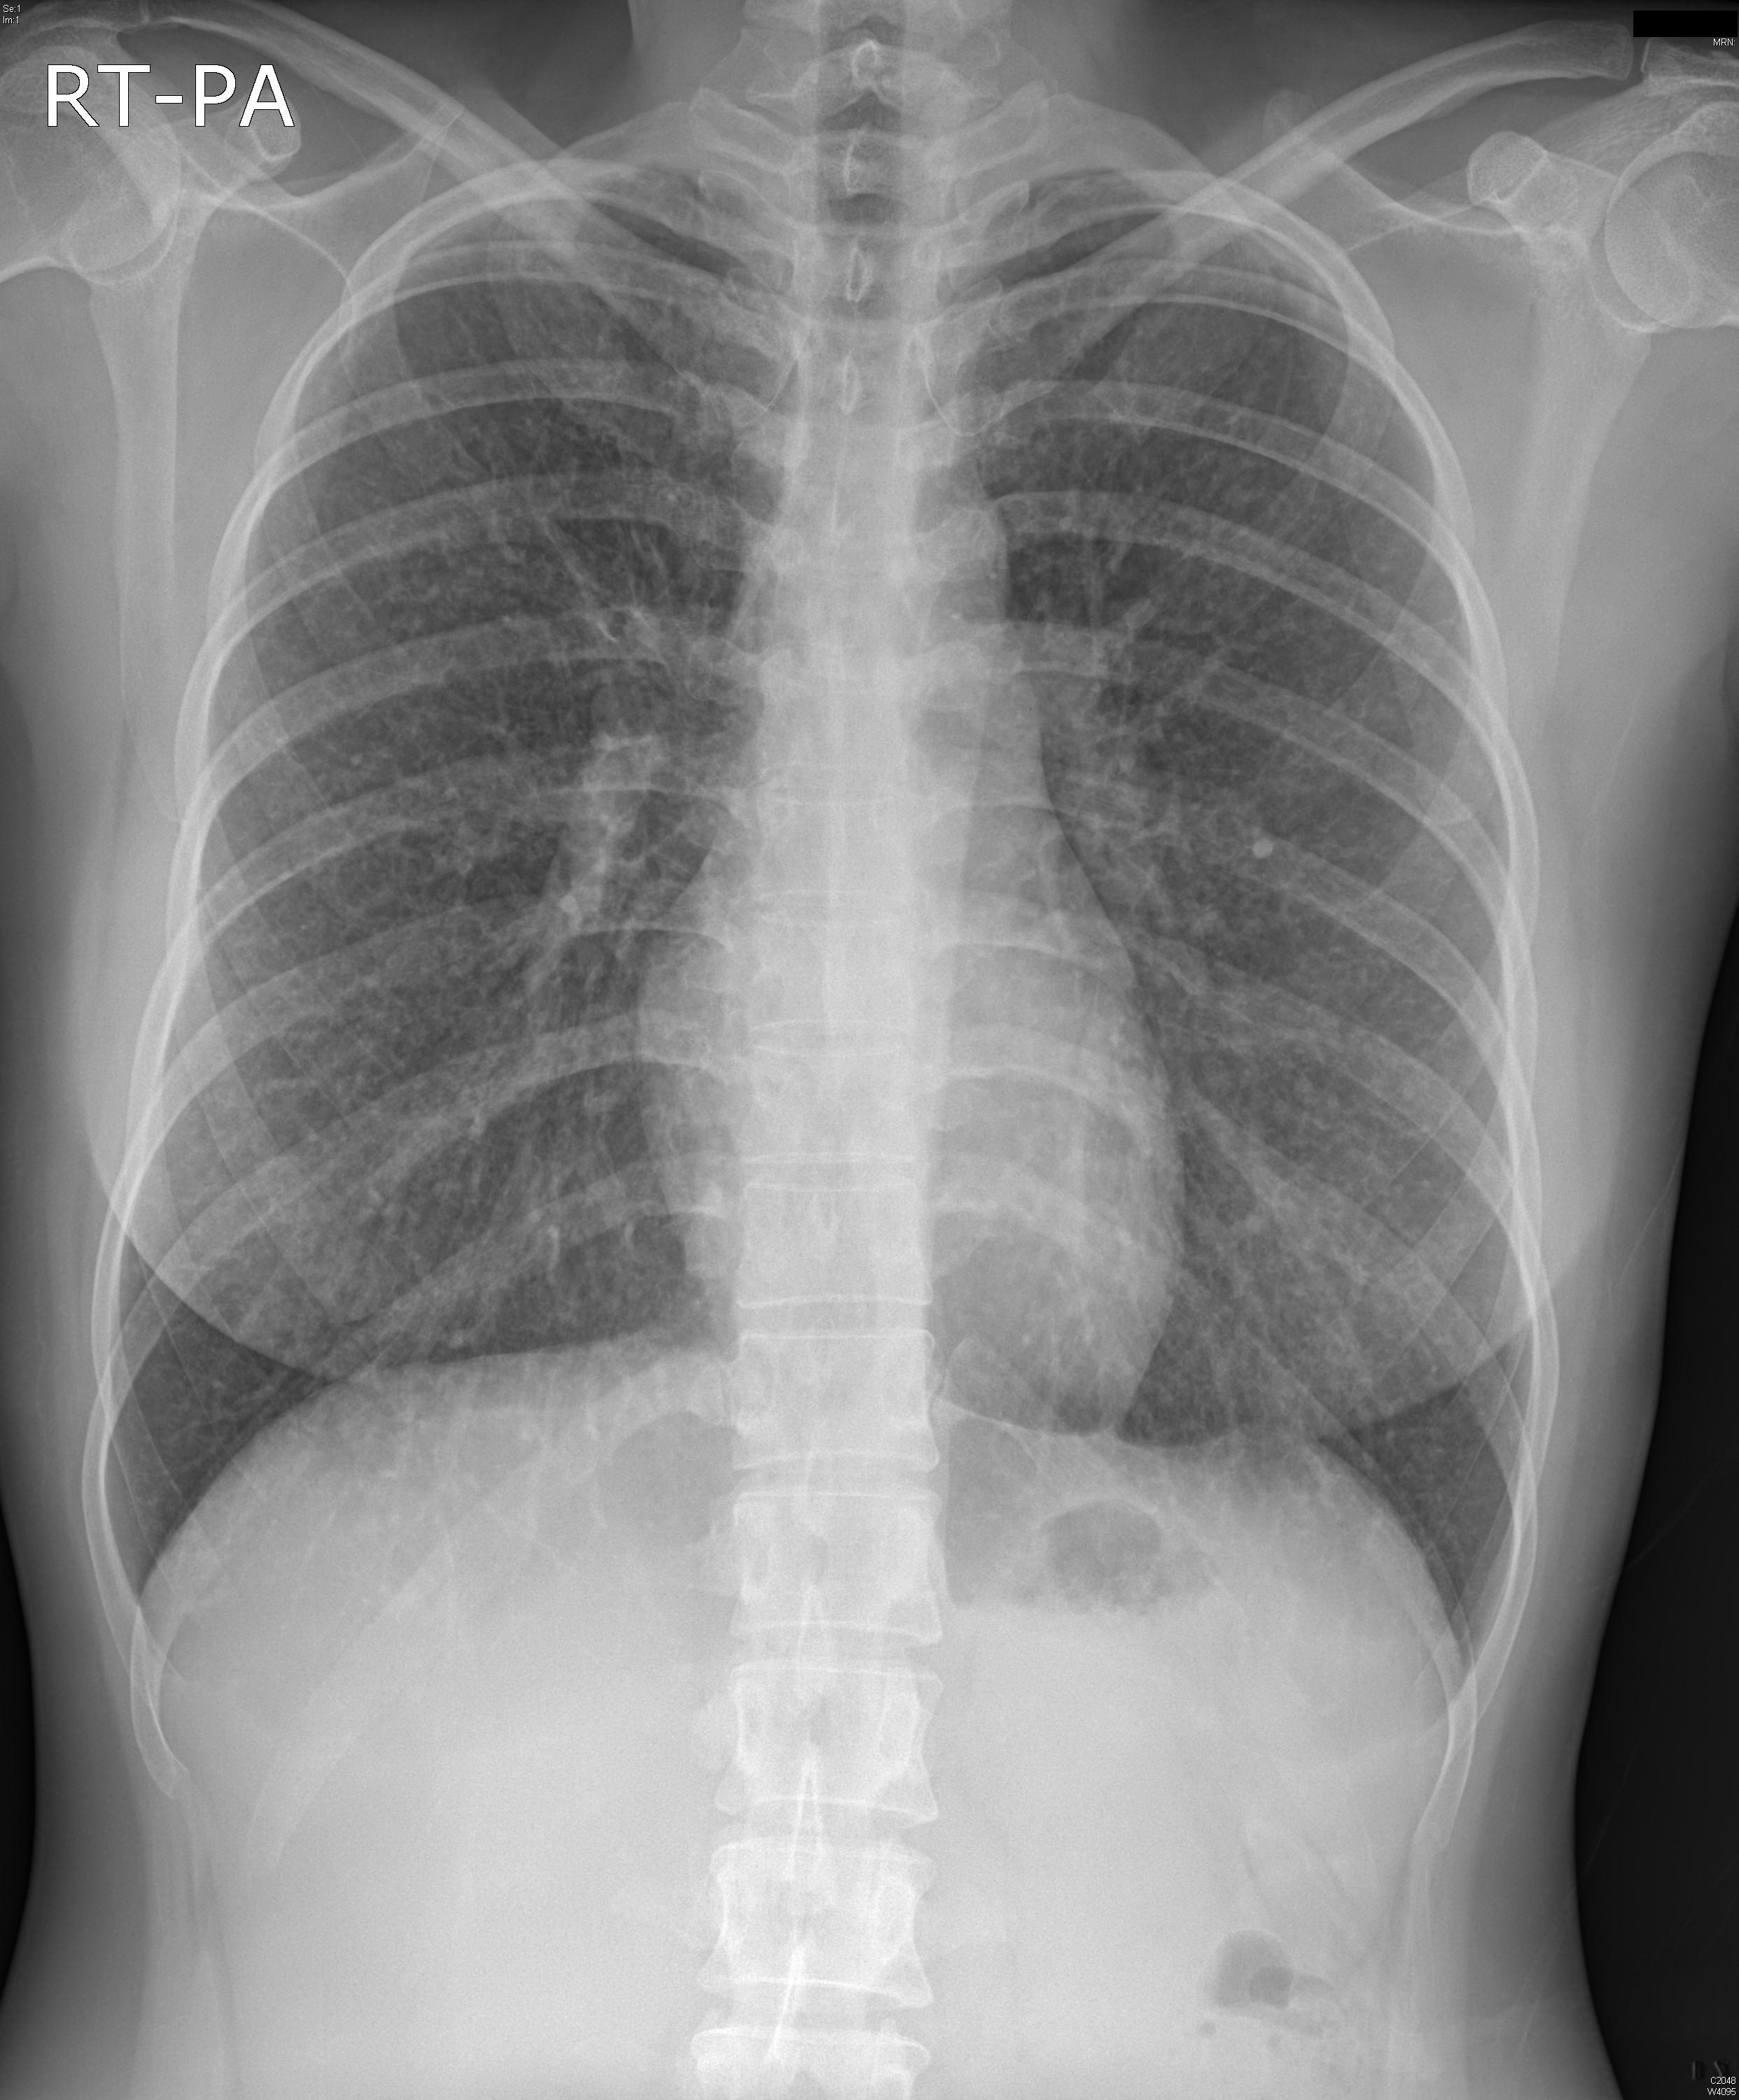

34¼¼ ¿©È¯.

°Ç°¨°ËÁø»ó CXR ÀÌ»ó ¼Ò°ßÀ¸·Î º»¿ø ³»¿ø.

CXR »ó  scattered nodular opacity over the whole lung ¼Ò°ßº¸¿©

Chest CT ÃÔ¿µ ÇÏ¿´À½.

°´´ã°Ë»ç ¹× ±â°üÁö ³»½Ã°æ °Ë»ç»ó AFB smear À½¼º ¼Ò°ß º¸¿´À¸¸ç,

°æÇèÀûÀ¸·Î Tb medication ½ÃÀÛÇÏ¿´À¸³ª °áÇÙ Ä¡·á ÇÑ´Þ ÈÄ¿¡µµ È£Àü ¾ø°í,

Mycobacterial culture ¿¡¼­µµ µ¿Á¤µÇ´Â ±ÕÁÖ ¾ø¾úÀ½.